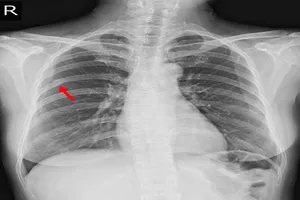

10. 기흉

가슴 통증이 갑자기 발생하고 호흡이 가빠진다면, 기흉을 의심해 볼 수 있습니다. 기흉은 폐에서 공기가 새어 나와 흉강에 차면서 폐가 쪼그라드는 질환으로, 마치 풍선에 구멍이 난 것처럼 폐에 공간이 생기는 현상입니다. 특별한 원인 없이 발생하는 경우가 많으며, 마르고 키가 큰 남성에게서 자주 나타납니다. 기흉의 치료는 질병의 정도에 따라 다르지만, 조기에 발견하고 적절한 치료를 받으면 대부분 완치될 수 있습니다. 따라서 가슴 통증이 지속되거나 호흡이 불편하다면 즉시 병원을 방문하여 정확한 진단을 받고, 필요한 치료를 받는 것이 중요합니다.